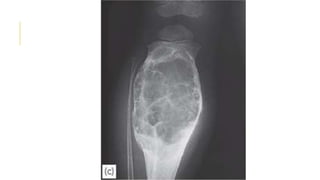

GIANT-CELL TUMOR

Giant-cell tumour is a lesion of uncertain origin that appears

after the end of bone growth.

Most commonly in the distal femur, proximal tibia, proximal

humerus and distal radius.

About one-third of these tumors remain truly benign; one-third

become locally invasive and one third metastasize.

Present as pain at the end of a long bone; sometimes there is

slight swelling.

Pathological fracture occurs in 10–15% of cases.

x-ray show a ‘cystic’ (i.e. radiolucent) area situated eccentrically

at the end of a long bone. Unlike any of the other ‘cystic’ lesions,

it always extends right up to the subchondral bone plate.

Treatment : well defined lesion with benign histology could be

treated by curettage and bone grafting While aggressive lesions

GIANT-CELL TUMOR Giant-cell tumouris a lesion of uncertain origin that appears after the end of bone growth. Most commonly in the distal femur, proximal tibia, proximal humerus and distal radius. About one-third of these tumors remain truly benign; one-third become locally invasive and one third metastasize. Present as pain at the end of a long bone; sometimes there is slight swelling. Pathological fracture occurs in 10–15% of cases. x-ray show a ‘cystic’ (i.e. radiolucent) area situated eccentrically at the end of a long bone. Unlike any of the other ‘cystic’ lesions, it always extends right up to the subchondral bone plate. Treatment : well defined lesion with benign histology could be treated by curettage and bone grafting While aggressive lesions